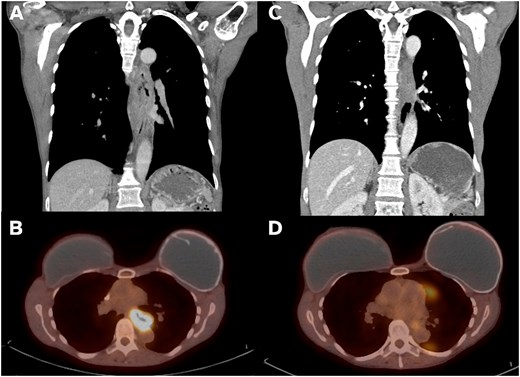

A 54-year-old non-smoking female presented with food impaction and progressive dysphagia. Workup revealed a T3N1M0 circumferential keratinizing invasive SCC of the mid-esophagus extending from 27-cm to 36-cm from the incisors. Pathologic-appearing lymph nodes were noted on endoscopic ultrasound. Computed tomography (CT) imaging reported an 8.6-cm long esophageal mass starting above the carina and adjacent but not involving the thoracic aorta (Fig. 1A). The mass was FDG avid (SUV 15.4) without distant metastases (Fig. 1B). Immunohistochemistry showed intact mismatch repair proteins, microsatellite stability, and low PDL1 expression. The patient received neoadjuvant CROSS protocol (carboplatin/paclitaxel and 23 fractions of 41.4 Gy of radiation). Repeat imaging showed significantly improved wall thickening (Fig. 1C) and decreased FDG avidity (SUV 3.2, Fig. 1D). Endoscopy showed a 10-mm mid-esophageal stricture with repeat negative biopsies. The planned transhiatal esophagectomy was converted to a right thoracotomy intraoperatively due to the esophagus being densely adherent at the carina and descending thoracic aorta. The esophagectomy was completed trans-thoracically avoiding injury to the trachea or aorta and securing clear margins. The stomach was brought up through the posterior mediastinum and anastomosed in the neck to the cervical esophagus. The patient recovered uneventfully and was discharged on postoperative day 10.

Imaging findings on presentation vs post-neoadjuvant therapy. (A) Coronal CT imaging showing 8.6-cm long esophageal mass. (B) PET imaging with mid-esophageal mass with SUV 15.4. (C) Post-CROSS protocol esophageal mass with significantly improved wall thickening on coronal CT. (D) Post-CROSS PET with decreased FDG avidity at the level of the mid esophagus.